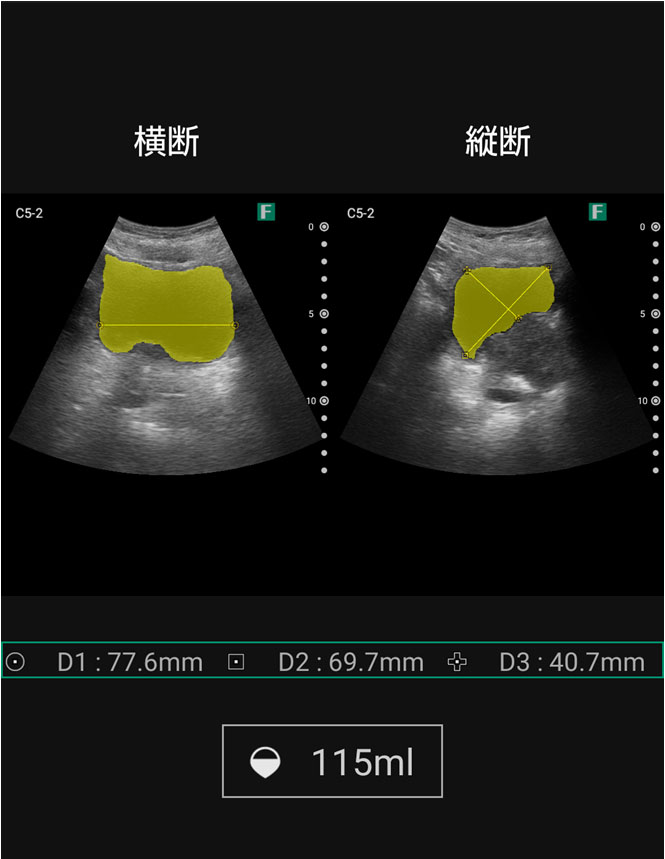

視診を行い下腹部に軽度の膨隆が確認できましたが体外から出ているカテーテルには明らかな閉塞を認めませんでした。そこで、iViz airで観察したところ、膀胱内に約400mlの残尿を認めカテーテル閉塞による腎後性腎不全と診断を確定させることができました。尿道カテーテルを抜去した際、外見からは見えないカテーテルの先端部分に沈殿物を認め、閉塞の原因であるとわかりました。その後尿道カテーテルの交換を行うと残尿の排出ともに腹痛は消失し、無事に帰宅されました。iViz airでの観察が尿閉の確定診断につながった症例です。